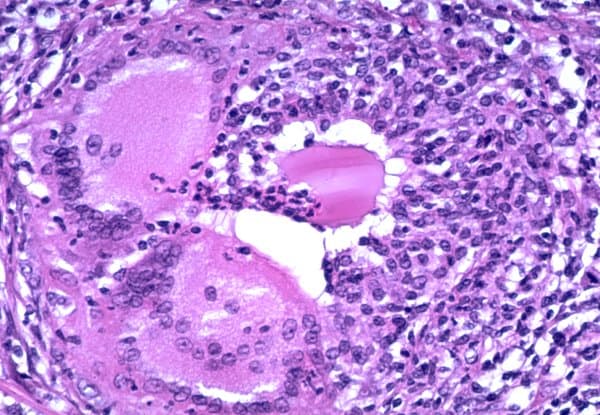

Une thyroïdite est une inflammation de la glande thyroïde. Il en existe plusieurs sortes que l'on distingue par leurs origines et leurs effets. Selon une étude cas-témoins récente (publication 2020), basée sur l'étude de cas de goitre, de thyrotoxicose, d'hypothyroïdie et de thyroïdite, comparés à témoins tirés des mêmes zones d'étude (utilisation élevée ou faible de pesticides), une exposition (professionnelle ou environnementale) accrue aux pesticides est associée à un risque accru de maladies thyroïdiennes. Les pesticides perturbateurs endocriniens exposent notamment à des changements dans les taux d'hormones thyroïdiennes circulantes (T3, T4) et de thyréostimuline (TSH). Il s'agit d'une inflammation chronique de la glande qui provient d'un phénomène d'auto-immunité et qui touche surtout les femmes. On retrouve un goitre non douloureux mais dur. Le principal problème sera l'hypothyroïdie (qui peut n'apparaître que tardivement) que l'on combat généralement par la prise d'hormones thyroïdiennes (comprimés) afin d'apporter les hormones manquantes et de permettre la diminution du volume du goitre. Le risque de tumeur (évolution cancéreuse) n'est pas à écarter. Thyroïdite de Hashimoto Il s'agit d'une inflammation de la glande thyroïde, peu courante et à prédominance féminine, probablement d'origine virale (infection ORL de type rhinopharyngite). Bénigne mais douloureuse (très vive au niveau cervical), cette maladie s'accompagne de fièvre et une augmentation de la taille de la glande. Lors de l'investigation, on constate un tableau spécifique avec une scintigraphie blanche (non fixation) et un dosage de TSH bas en début de la maladie. La maladie évolue généralement en deux phases : une première phase d’hyperthyroïdie (TSH basse, T4 augmentée) par libération des hormones thyroïdienne dans la circulation sanguine à la suite de la réaction immunitaire attaquant la glande, puis une seconde phase de retour à l'euthyroïdie ou évoluant vers l'hypothyroïdie, pouvant être passagère ou définitive.